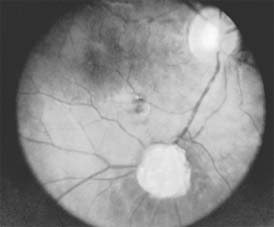

MACULAR EDEMA

Retinal edema involving the macula may be associated with a variety of intraocular inflammatory diseases, retinal vascular diseases, intraocular surgery, inherited or acquired retinal degenerations, medications, macular membranes, or unknown causes. Macular edema may be diffuse, with nonlocalized intraretinal fluid causing thickening of the macula. When edema fluid accumulates in honeycomb-like spaces of the outer plexiform and inner nuclear layers, it is called cystoid macular edema. On fluorescein angiography, fluorescein dye leaks from the perifoveal retinal capillaries and accumulates in a flower-petal pattern about the fovea (Figure 10-4).

Figure 10-4

Figure 10-4: Flower-petal pattern of fluorescein dye in a patient with cystoid macular edema after cataract surgery.

The most widely recognized association with cystoid macular edema is intraocular surgery. Approximately 50% of eyes undergoing uneventful intracapsular cataract extraction and 20% of eyes undergoing extracapsular cataract extraction develop angiographic cystoid macular edema. Clinically significant edema usually occurs within 4-12 weeks postoperatively, but in some instances its onset may be delayed for months or years. Many patients with cystoid macular edema of less than 6 months' duration have self-limited leakage that will resolve without treatment. Topical or local (or both) anti-inflammatory therapy may be of value in restoring visual acuity in some patients with chronic postoperative macular edema. YAG laser vitreolysis (see Chapter 24) and surgical vitrectomy may be of benefit when the macular edema is associated with vitreous tissue incarcerated in the cataract wound or adherent to anterior segment structures. When an intraocular lens implant is the cause of postoperative macular edema due to its design, positioning, or inadequate fixation, removal of the lens implant can be considered.